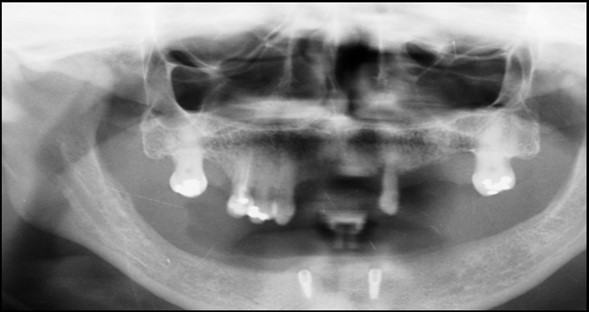

Post operatively after 3 months, osseointegration was evaluated clinically and radiographically (Figure 5a,b) and the implants were well prepared to receive the prosthesis. The second stage surgery was performed in which cover screws were removed and healing abutment were inserted into the implants (Figure 6). After a time period of two weeks, peri-implant soft tissue healing was examined, and existing denture was relined after relieving at the abutment site. Later, the healing abutment is removed using a 1.25 mm hex driver. Internal portion of the implant is irrigated and dried to make sure if it is free of debris and soft tissue. A periodontal probe was used to measure the gingival cuff height at the right and left canine site of implant location. Selected ball abutment were placed onto each implant using 1.25 mm hex driver and 30 Ncm torque wrench (Figure 7A).

Figure 6.Panoramic radiograph after the insertion of two implants